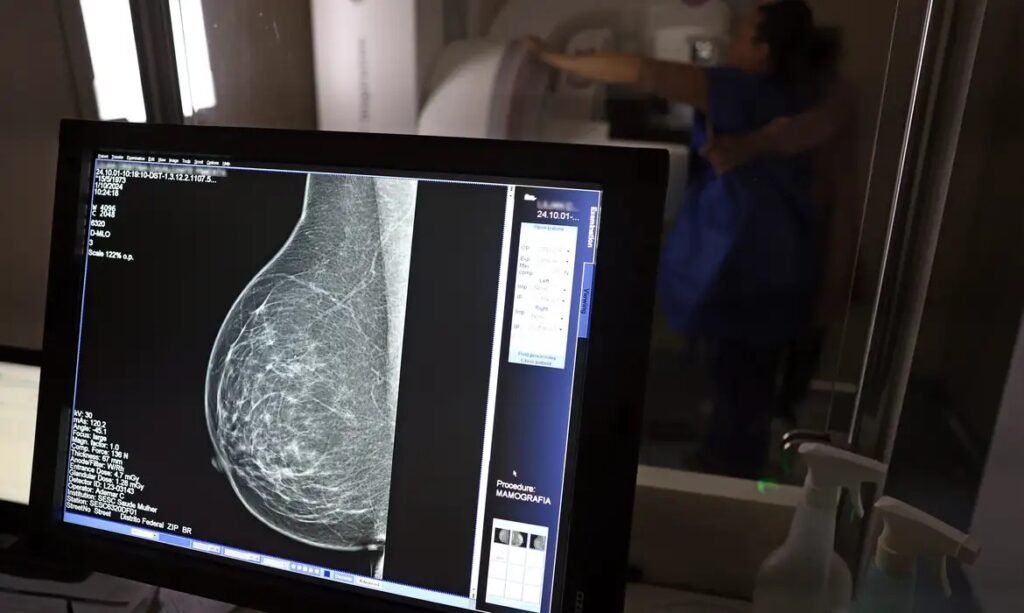

As mamografias via SUS em pacientes com menos de 50 anos, de acordo com a pasta, representam 30% do total, o equivalente a mais de 1 milhão apenas no ano de 2024.

Outra medida anunciada é a ampliação da faixa etária para o rastreamento ativo – quando a mamografia é solicitada de forma preventiva a cada dois anos. A idade limite, até então, era 69 anos. Agora, passa a ser 74 anos. Dados do ministério revelam que quase 60% dos casos de câncer de mama estão concentrados entre 50 e 74 anos.

Os números mostram que, em 2024, cerca de 4 milhões de mamografias para rastreamento e 376,7 mil exames diagnósticos foram realizados no SUS.